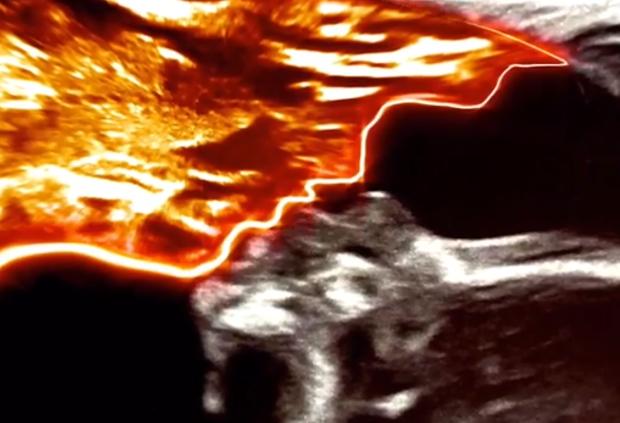

近日,香黛儿在社交媒体上发布了自己怀孕20周的B超图,她的朋友们在这张图上看到了神奇的一幕。

香黛儿说:“我刚把图片放在网上大概30秒后,有一个朋友给我留言说,‘有个天使在亲吻你的宝宝!’老实说,这个消息让我既意外又吃惊,于是我又仔细看了看这张图,竟真的看到了我已逝的父亲在亲吻我女儿。”

照片中,孩子的头顶上有一个清晰可见的轮廓,神似十年前香黛儿的父亲查克,抱着她的第一个女儿麦莉·帕切科的照片。当时,查克戴着一顶红帽子,认真地望着那个婴儿。

香黛儿拿着超声波说:“照片里可以看到我爸爸独特的鼻子、脸颊。你看,这是他下巴上鼓起的小圆球,我爸爸的下巴长得很特别。”